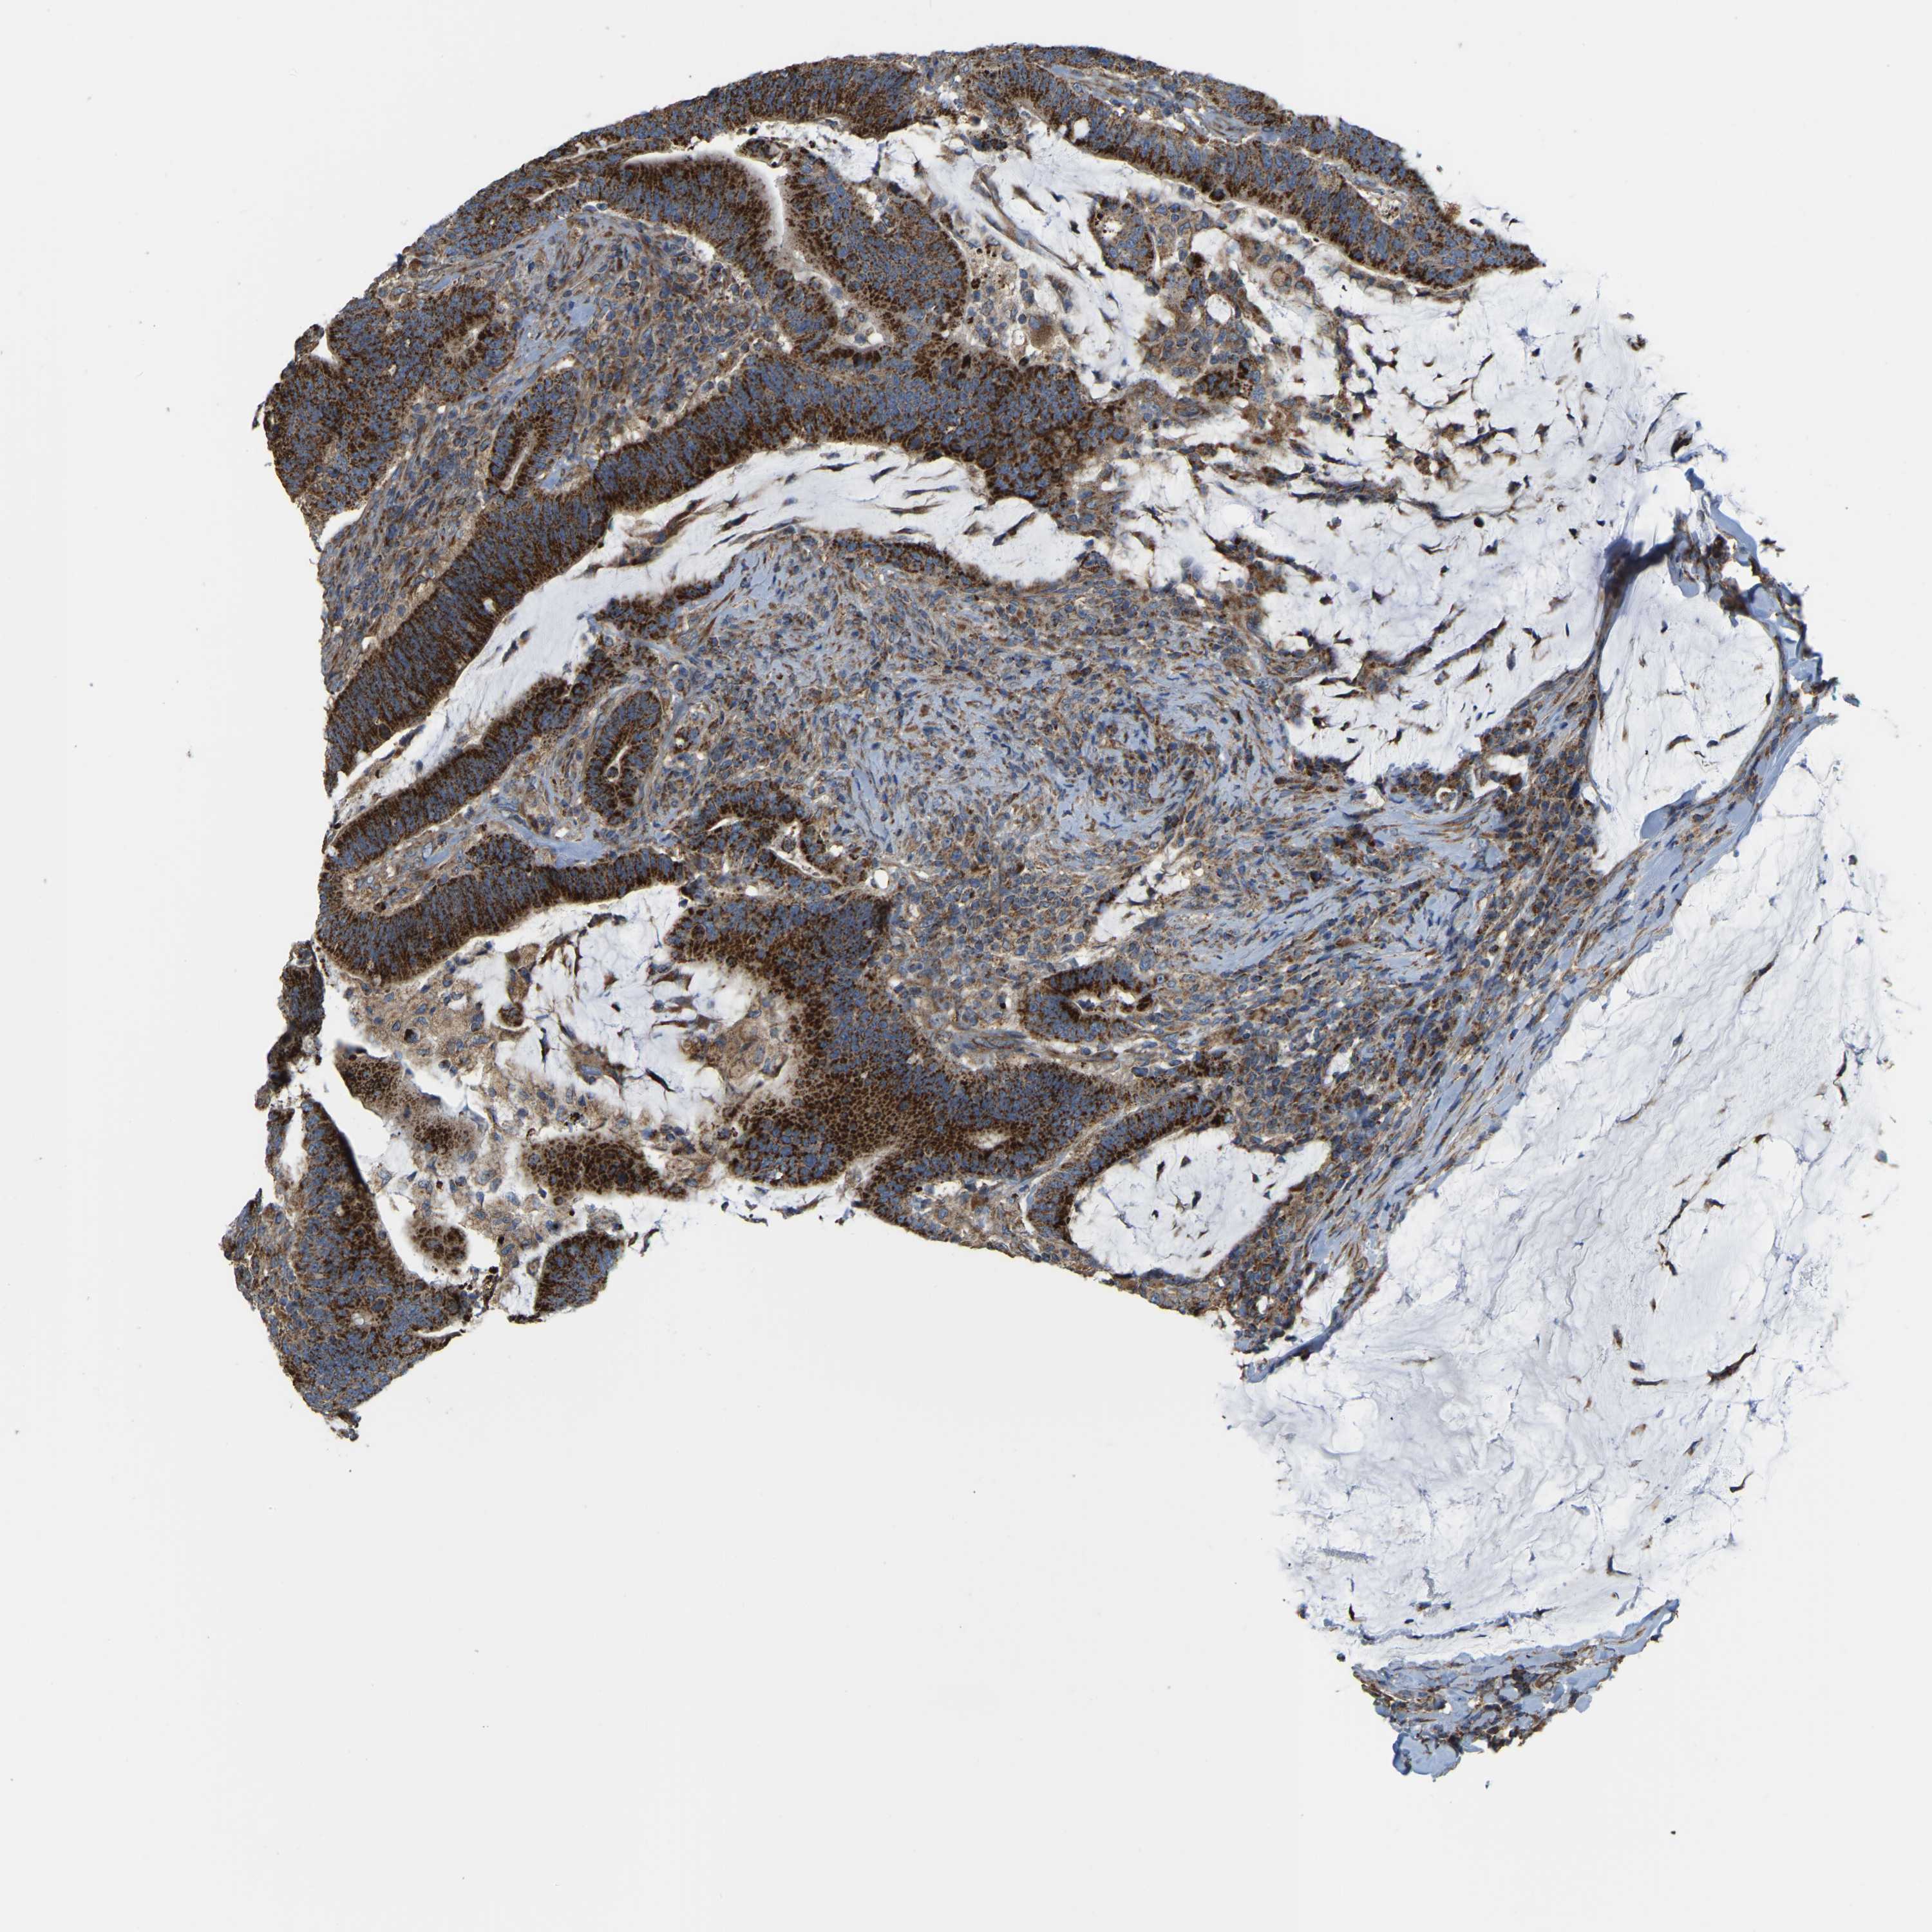

Colorectal cancer

Rectum adenocarcinoma

TCGA RNA samplesi

RNA-seq data is reported as average FPKM (number Fragments Per Kilobase of exon per Million reads), generated by the The Cancer Genome Atlas (TCGA) .

Normal distribution across the dataset is visualized with box plots, shown as median and 25th and 75th percentiles. Points are displayed as outliers if they are above or below 1.5 times the interquartile range. FPKM values of the individual samples are presented next to the box plot.

Average pTPM 122.4

Number of samples 88